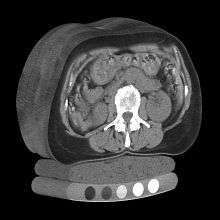

Dual use of CT images

Several studies have shown that bone density may be measured by QCT using CT images that were ordered for other purposes. Using pre-existing images, including CT colonography exams,[14] QCT allows for bone density screening without submitting the patient to any additional radiation exposure. The feasibility of using routine abdominal contrast-enhanced CT scans for the evaluation of bone density by QCT has also been demonstrated.[15]